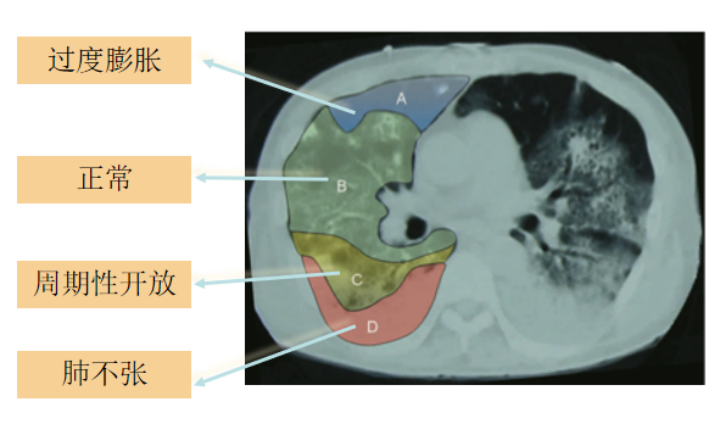

在机械通气参数设置时,不仅要符合病理生理的改变,还要符合患者个体化特点。以ARDS为例,典型的ARDS会出现肺顺应性下降,但通过CT影像发现这种肺顺应性的下降并非均匀、一致的,而是分层的,例如在腹侧区域,可能表现为过度膨胀;在腹侧下一区域,可能是正常通气;在靠近背侧区域,可能是周期性开放,而在背侧区域,实际上是处于肺不张状态。这种形态学变化提示我们,典型ARDS肺顺应性下降的变化实际上是病变与通气的不均一。

在机械通气时,我们测量的静态肺顺应性实际上是将肺看作为一个整体,无论如何调整呼吸机参数,仍无法知道其内部的具体变化。而对于局部肺顺应性,通过EIT的监测能够看到以电极束带为核心整个肺的20%~30%的区域中动态图形的变化,同时,它能够最大限度地将肺还原形态学的特点。因此,无论是分层还是区分象限,实际上都遵循了肺形态学的特点和不同疾病通气的特点。所以,EIT的优势在于其不仅能将肺看成一个整体,而且能考虑中间的不同变化。